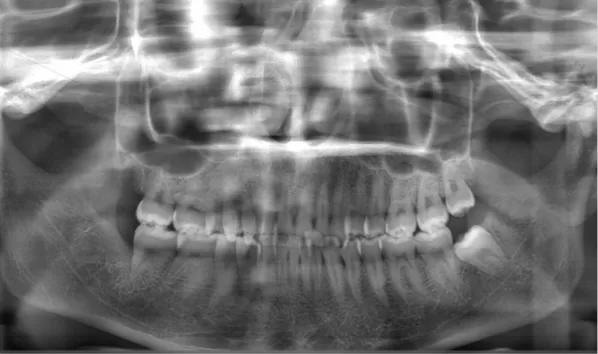

Rayons X avant le traitement

[Radiographie panoramique/Céphalogramme latéral]